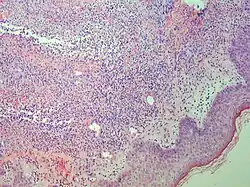

| Kaposi’s sarcoma in patch stage | The patch stage typically shows irregular proliferation of jagged vascular channels in the dermis below an integral epidermis. The so-called promontory sign is sometimes found in patch stage lesions and denotes vascular spaces surrounding pre-existing blood (see image).[23]

vessels |

|